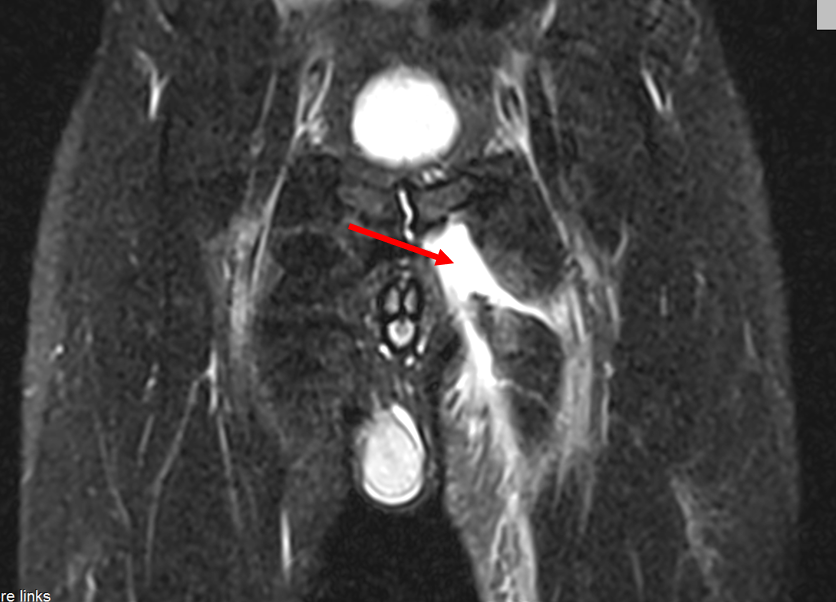

图1 骨盆MRT显示出明显的长收肌血肿-红色箭头

54岁男性患者,网球比赛中,为了打削球,向前跨了一大步。动作初期,他感到左腹股沟刺痛,同时听到类似于“撕纸”的声音,这导致其腿部功能完全丧失,以至于不得不在对手的帮助下离开球场。核磁共振成像(MRI)显示病人内收肌长肌不完全撕裂,如果其功能持续丧失,创伤外科医生会考虑手术治疗。患者每天接受1次淋巴引流治疗,每次1小时并持续8天后,血肿几乎消失。创伤后6周,患者重返网球运动。在此期间,他只是在跨步较大的情况下,才会感觉到“轻微的牵拉”,而两周后这种牵拉感也完全消失了。